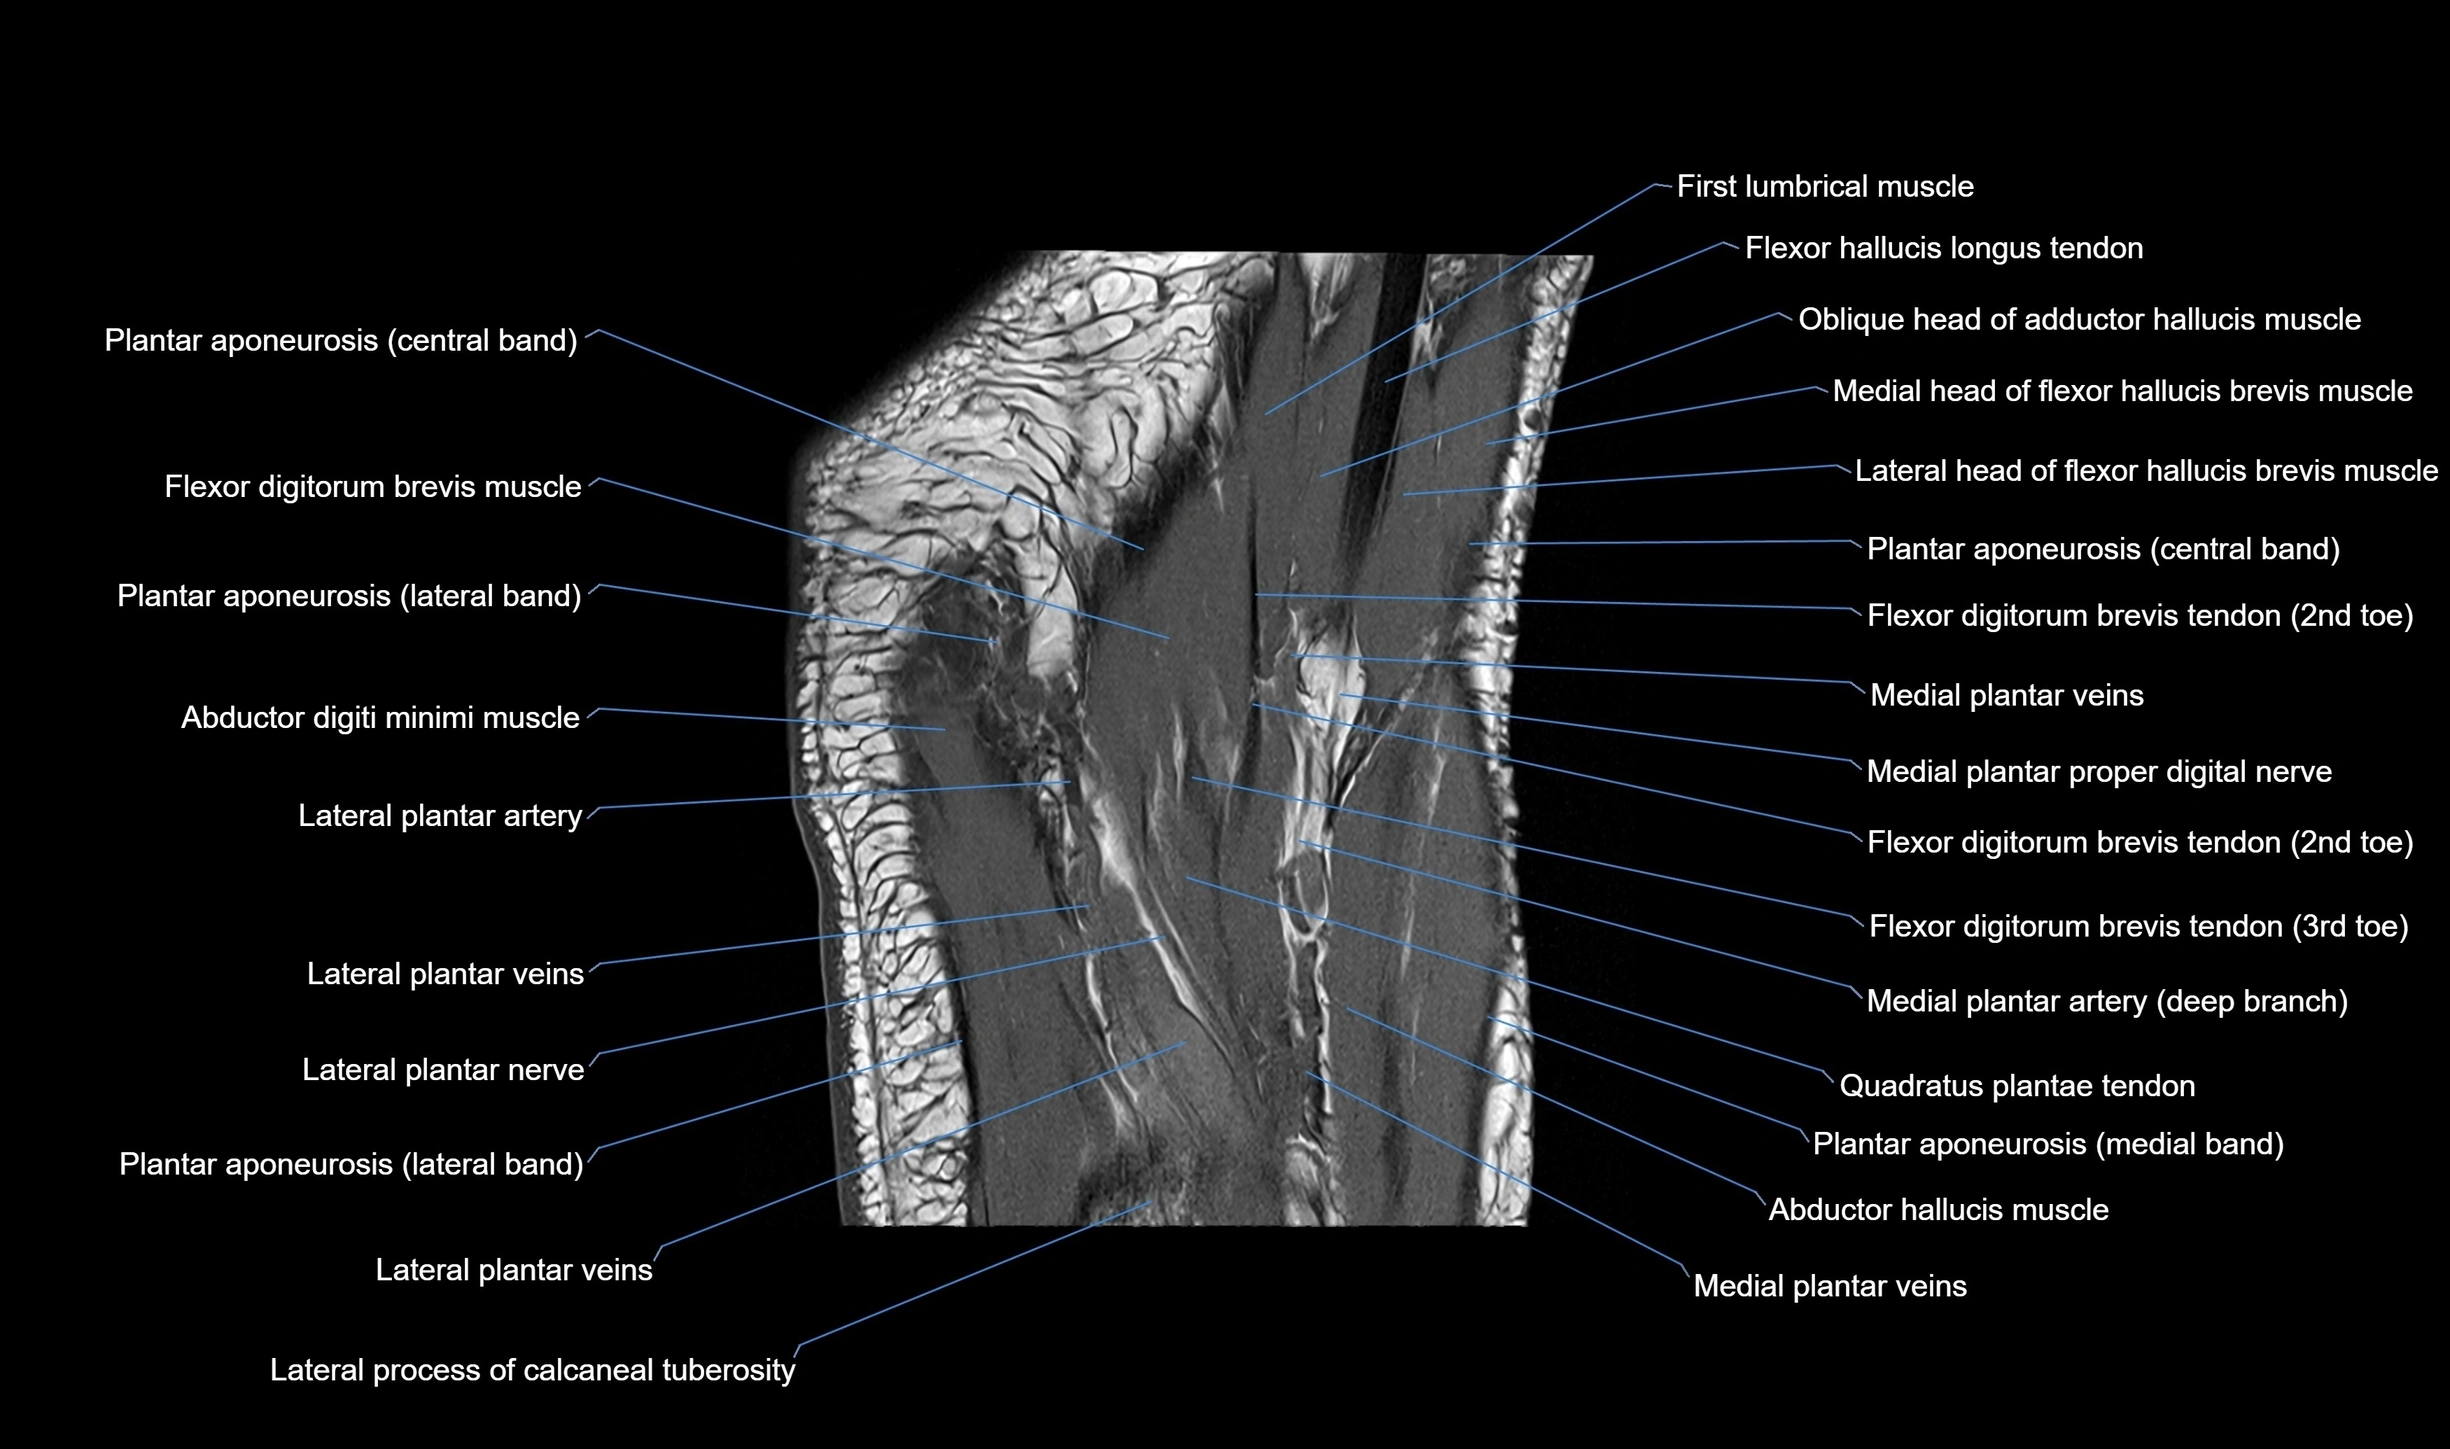

MRI image